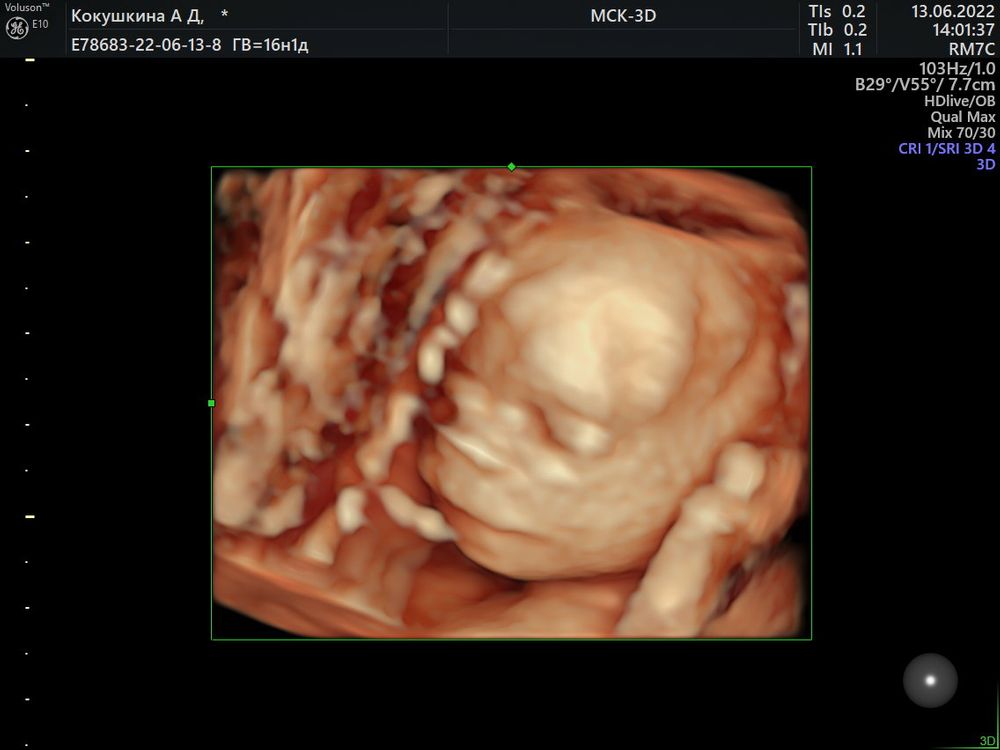

Узнали пол малыша в 16-17 недель🥰

На первом и правда не видно половой бугорок.

Поздравляюююю😍😍😍🌸🌸🌸 это уже 3 пост, где пишут, что по первому скринингу возможно девочка, по второму уже точно мальчик😂 у меня тоже так получилось🤗🤗🤗